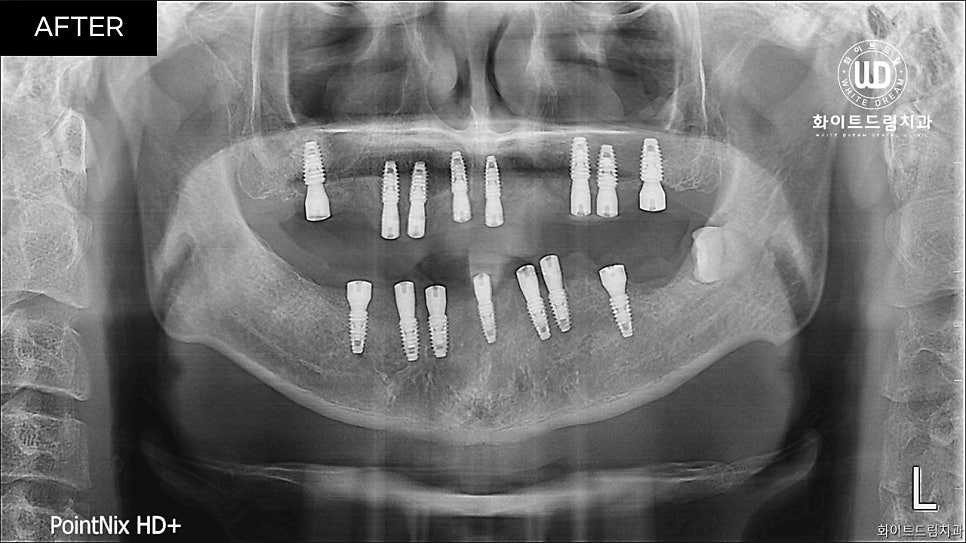

주의사항을 잘 따라 주신 만큼 아무는 기간동안 별도 염증없이 잘 아물었습니다.

안정화 기간을 거쳐 골 유착도 검사를 해보니 알받은 결과가 나와 임플란트 보철 인상채득을 진행할 수 있었습니다.

중간 지주대를 픽스처에 연결해주고 2주뒤 최종 보철물까지 올려주니 실제 치아와 비슷하게 기능적, 심미적으로 회복되었습니다.

진행한 치료 기간은 22년 6월부터 22년 12월까지 약 6개월 정도 소요되었습니다.

상악 2번 하악 1번 총 3번에 걸쳐 상악동 거상술과 뼈이식을 동반한 임플란트 식립을 진행했습니다. 그 후, 5개월 뒤 임플란트 보철 인상채득 후 2주 뒤에 보철을 마무리 해드렸습니다.